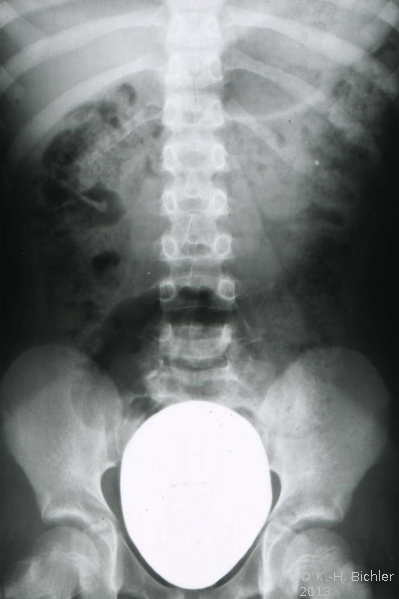

Bei dem 16 Jahre alten Jungen wurde aufgrund der ausgedehnten Ureterozele mit sekundärem partiellem Megaureter insbesondere Dilatation des Harnleiters und länger dauernden rezidivierenden Harnwegsinfekten eine offen Ureterozelenabtragung und Ureterreimplantation durchgeführt (Abbildung 7).